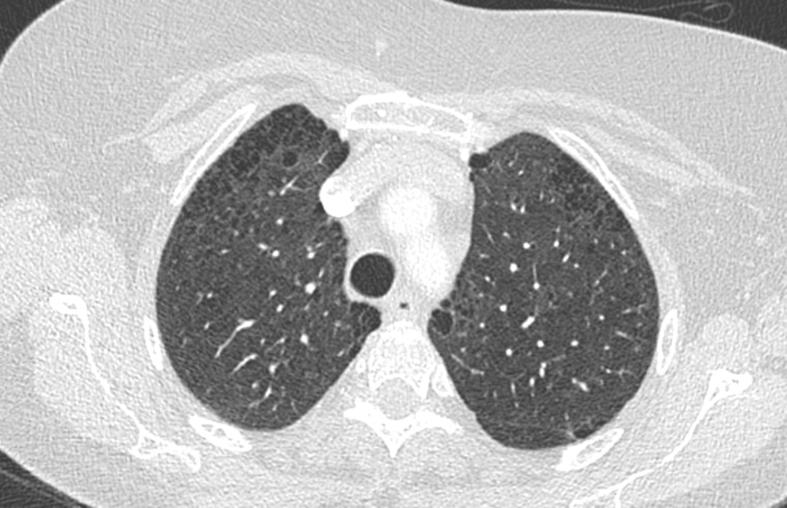

Neurofibromatosis type 1 (NF1) is a genetic disease in which pulmonary complications are rare, but severe, especially pulmonary hypertension (PH). The mechanisms underlying the onset of PH in patients with NF1 are unclear and might be multifactorial. In particular, the frequent presence of pulmonary parenchymal lesions makes etiological diagnosis of PH difficult. We describe here the case of a patient with NF1 admitted to our clinic with dyspnea and right heart failure revealing severe pre-capillary PH. Parenchymal lesions were mild and PH was attributed to pulmonary vascular involvement. Clinical and hemodynamic conditions of the patient improved under pulmonary arterial hypertension-specific combination therapy. This case suggests that treatment of PH due to pulmonary vascular involvement in NF1 may be aligned with recommendations for PAH treatment.

1型神经纤维瘤病(NF1)是一种遗传性疾病,其肺部并发症虽罕见但严重,尤其是肺动脉高压(PH)。NF1患者发生PH的潜在机制尚不清楚,可能是多因素的。特别是肺部实质病变的频繁出现使得PH的病因诊断困难。我们在此描述了一例NF1患者,因呼吸困难和右心衰竭入住我院,检查发现严重的毛细血管前PH。实质病变较轻,PH归因于肺血管受累。在肺动脉高压特异性联合治疗下,患者的临床和血流动力学状况得到改善。该病例表明,NF1中因肺血管受累导致的PH治疗可能与PAH治疗建议一致。